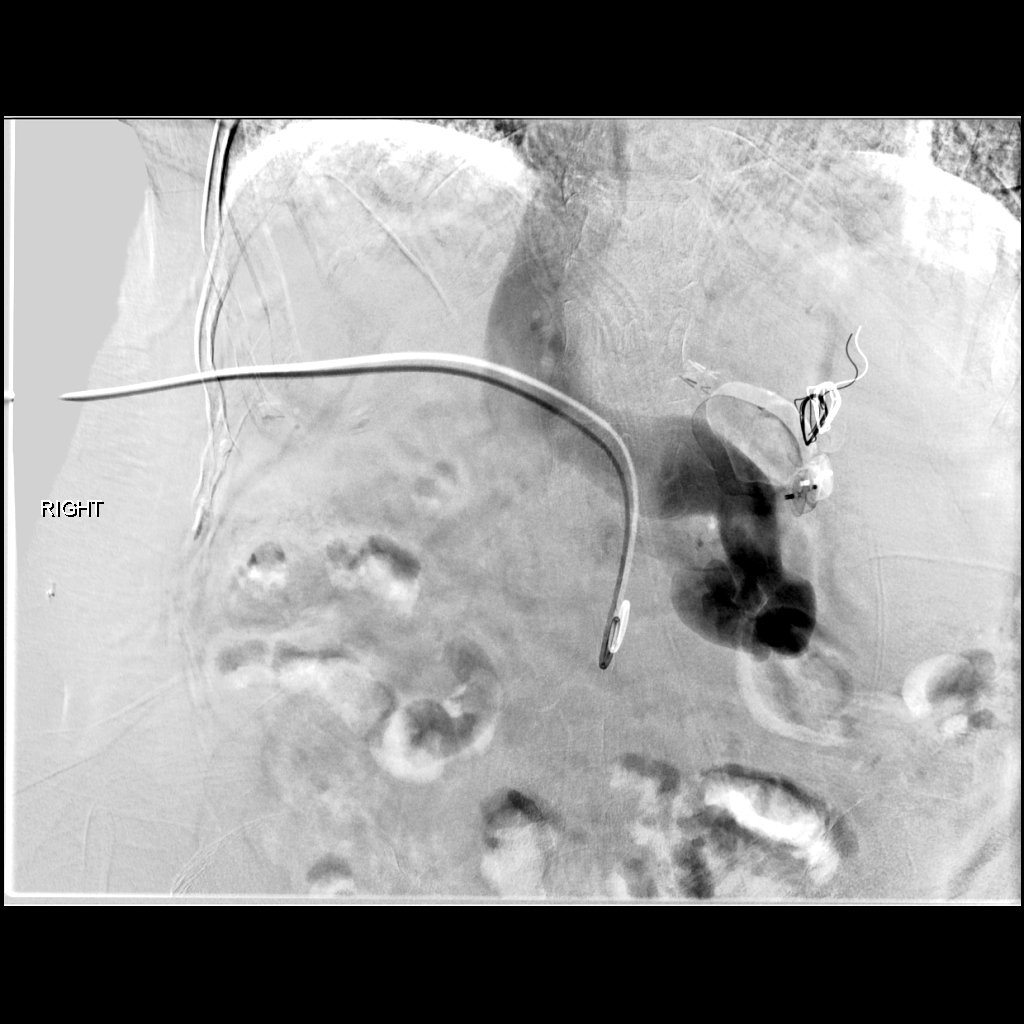

47 yo p/w massive PE s/p systemic tPA and persistent hypotension. Extensive right-sided PE on angio. Thrombus completely removed with FlowTriever mechanical thrombectomy. PA pressure decreased to 30mmHg from 64 mmHg immediately. #IRad @SIRspecialists @SIRRFS @SIR_ECS @JVIRmedia